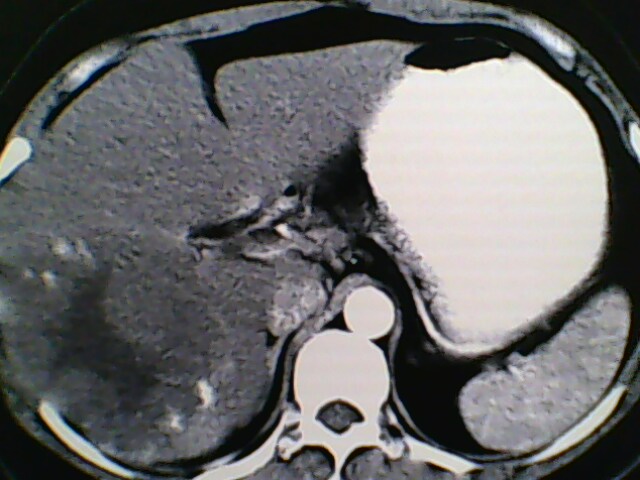

女,42岁,既往彩超检查肝血管瘤,做ct增强扫描,描述一下,依次为平扫,动脉期,门脉期,延长期

符合典型肝血管瘤强化表现

支持 肝右叶巨大肝血管瘤。

肝右叶巨大肝血管瘤。

肝右叶巨大肝血管瘤表现。